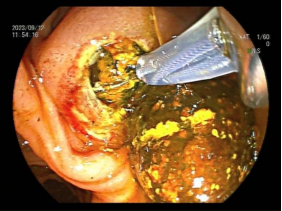

3.早期消化道肿瘤ESD技术

内镜下粘膜剥离术(ESD),具有超级微创、安全性高、住院时间短及费用低等优势,治疗早期胃癌、食管癌、大肠癌等病变,5年生存率超90%。

直肠巨大绒毛状腺瘤 内镜下粘膜剥离过程

粘膜剥离术后创面 剥离的巨大腺瘤